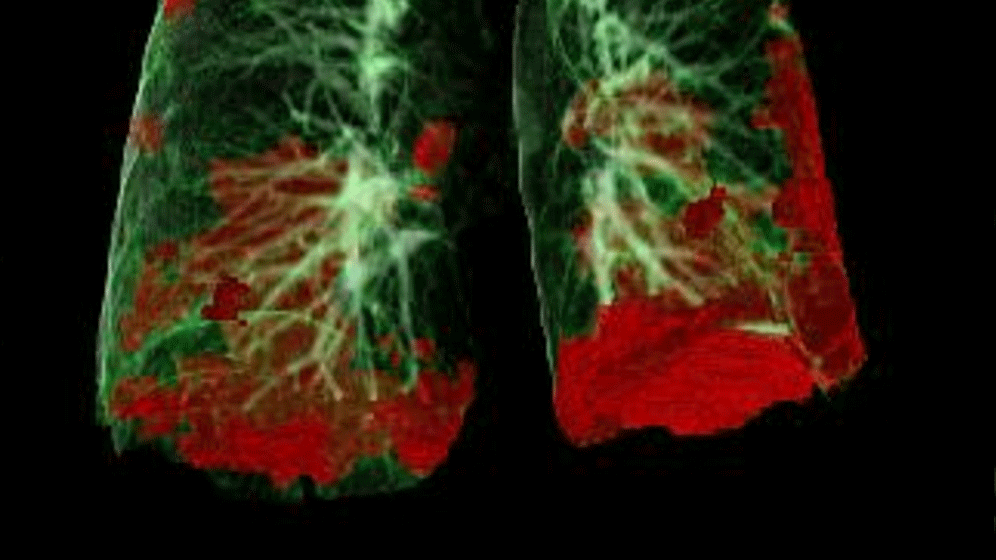

Das CT-Bild zeigt die durch SARS-CoV-2 geschädigten Lungenareale (in Rot). Typisch für COVID-19 ist die Schädigung der Lunge beidseits und basal (in den unteren Bereichen). Radiologie Innsbruck - D. Bullock

In Zusammenarbeit mit dem Team um den Radiologen Gerlig Widmann, zeigten sich in den CT-Untersuchungen sechs Wochen nach Krankhausentlassung bei 88 Prozent der Patient/-innen anhaltende leicht- bis mittelgradige strukturelle Veränderungen der Lunge, Diese bildeten sich allerdings im Zeitverlauf bei den meisten Patient/-innen deutlich zurück.  Es gibt derzeit keine Hinweise auf fortschreitende Lungenschäden, wie etwa zunehmende Vernarbungen. Ob die Veränderungen in der Lunge und die damit verbundene Einschränkung der Lungenfunktion vollständig abklingen werden, ist aktuell noch nicht zur Gänze zu beantworten und wird in weiteren Untersuchungen analysiert werden.